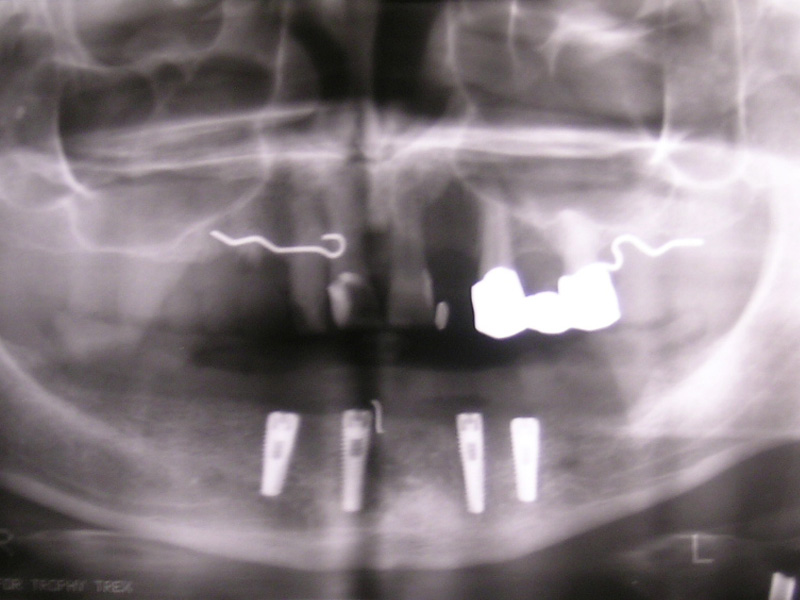

Implante - Galerie Foto

Radio-

grafii